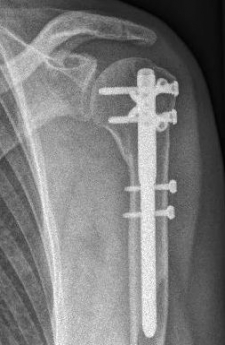

Proximaler Oberarmbruch7Proximaler Oberarmbruch8

Picture: In the above pictures, a slightly shifted subcapital humeral fracture was internally splinted using intramedullary nail. The left picture is a follow-up examination half a year after the accident and shows the complete healing of the fracture with correct position of the bone.